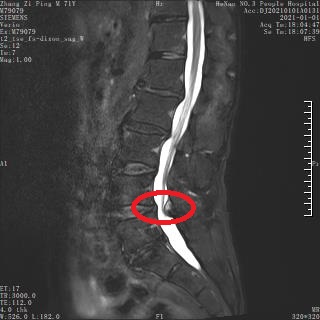

术前 MRI 1.jpg

术前 MRI 1